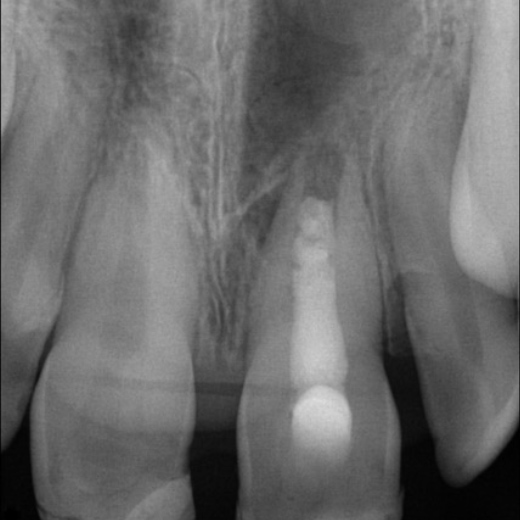

Fallbeispiel: Frontzahntraumata-Trauma im Alter von 9 Jahren mit Recall nach 22 Monaten

Frontzahntraumata sind im Kinder- und Jugendalter nicht selten. Bei noch nicht abgeschlossenem Wurzelwachstum können solche Zähne erfolgreich mit einer Revaskularisation behandelt und erhalten werden.